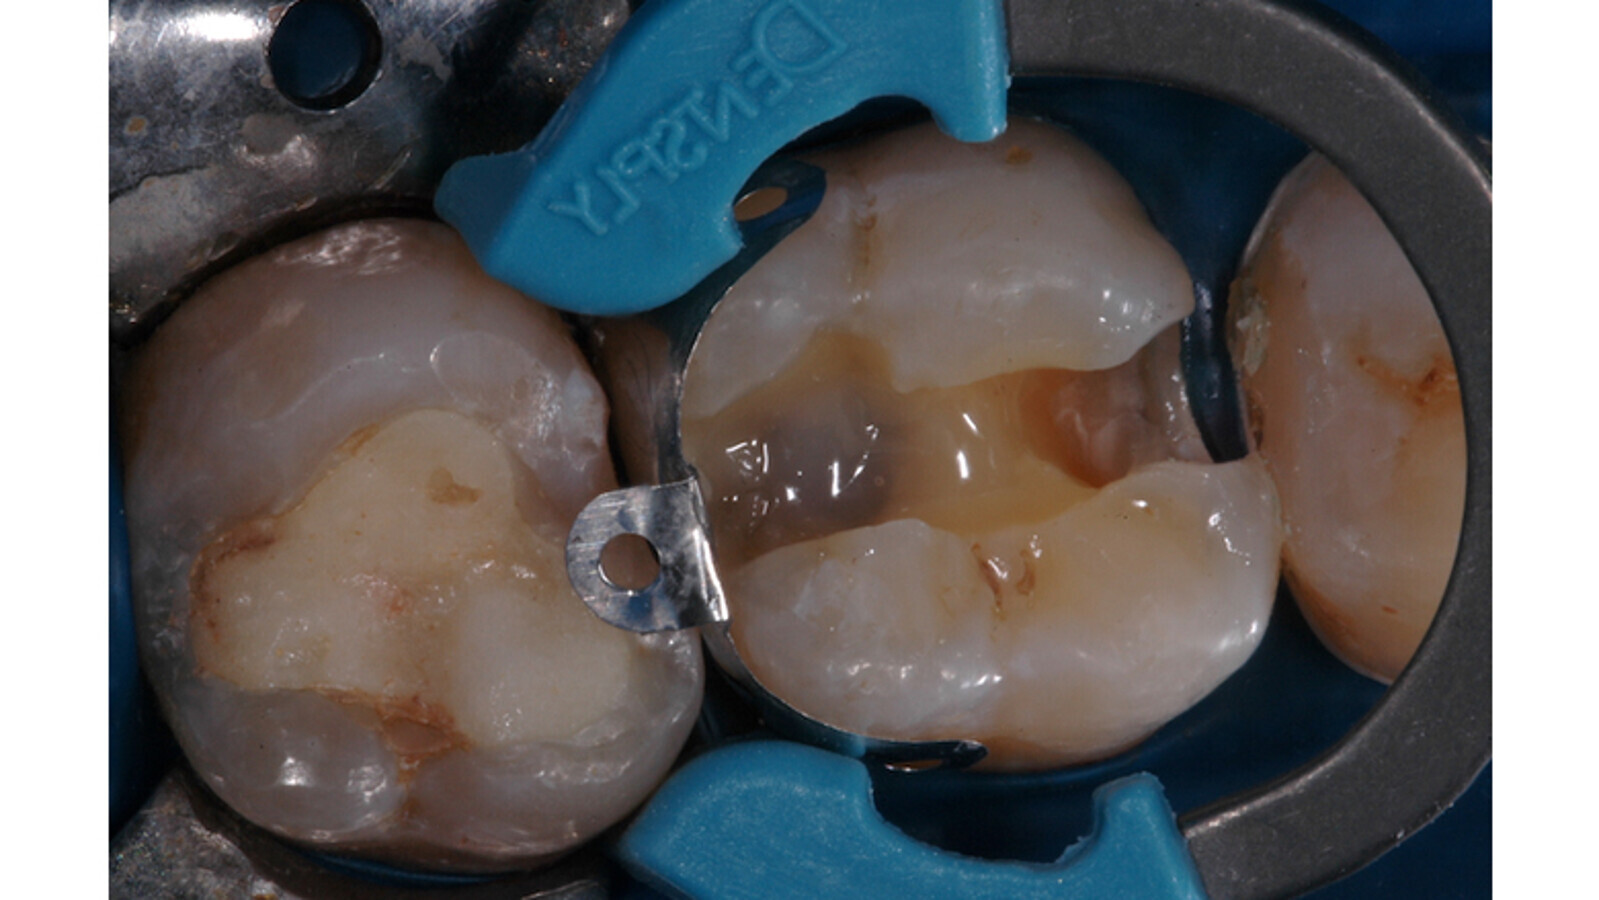

Foto 5. Preoperatorio: se observan caries proximales en la pieza 26.

Foto 6. Luego de la preparación cavitaria se observa el grabado ácido total y la protección de las piezecinas.

Foto 7. Aplicación del SDR flow en una de las cajas proximales. Se observan las matrices proximales V3.